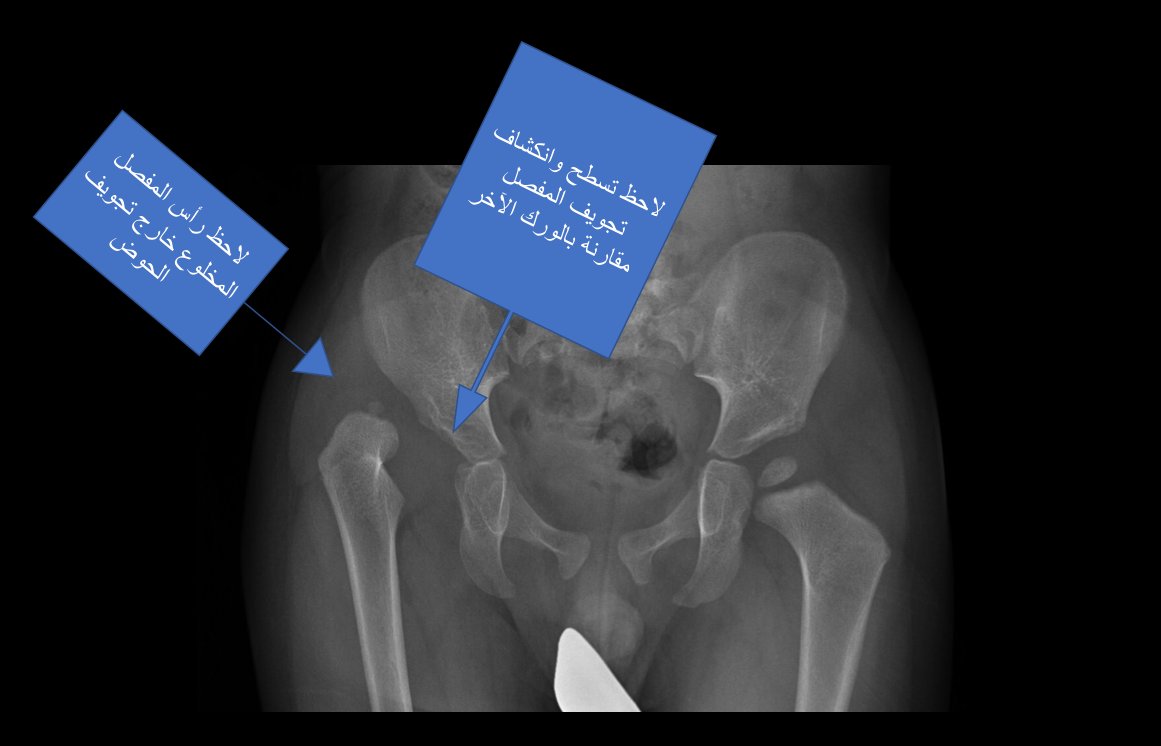

الخلع الولادي مشكلته الأولية تقع في النقص الخلقي-التطوري في تجويف (غطاء) المفصل ويتبع ذلك خروج رأس المفصل من مكانه الطبيعي ليكون مخلوعا

خلال الرد المغلق ، يتم إرجاع رأس المفصل لمكانه الطبيعي ، لكن غطاء المفصل يبقى كماهو ناقصا !

عندما يخبر الجراح والدي الطفل أن الرد المغلق نجح، هذا معناه أن رأس المفصل رجع واستقر في مكانه وهو الذي سيجعل الطفل يمشي بشكل طبيعي ، لكن ذلك لا يعني أن مفصل الورك أصبح طبيعيا بالكامل.

مفصل الورك الذي استقر رأسه في مكانه الطبيعي لكن تجويفه (غطاءه) بقي ناقص التكوين سيكون عرضة للاحتكاك والتآكل في عمر مبكرة قد لا تتجاوز سنوات الدراسة الثانوية .. حينها يعاني المصاب بآلام في مفصل الورك لا يمكن علاجها إلا بتبديل مفصل صناعي.

السؤال: ماهو مصير النقص الخلقي-التطوري في تجويف المفصل بعد نجاح الرد المغلق ؟

في أكثر من ٧٠ ٪ من الحالات، إذا استقر رأس المفصل في مكانه الطبيعي ، فإن غطاء المفصل يستجيب لذلك ويبدأ تدريجيا بالتعافي حتى يكتمل تطوره خلال سنة أو سنتين من الرد المغلق

إذا كان غطاء المفصل لا يستجيب، ولا يتحسن بعد الرد المغلق ، فمن المفترض تقديم علاج جراحي بسيط لتعديل غطاء المفصل في عمر لا يتجاوز ٦ سنوات